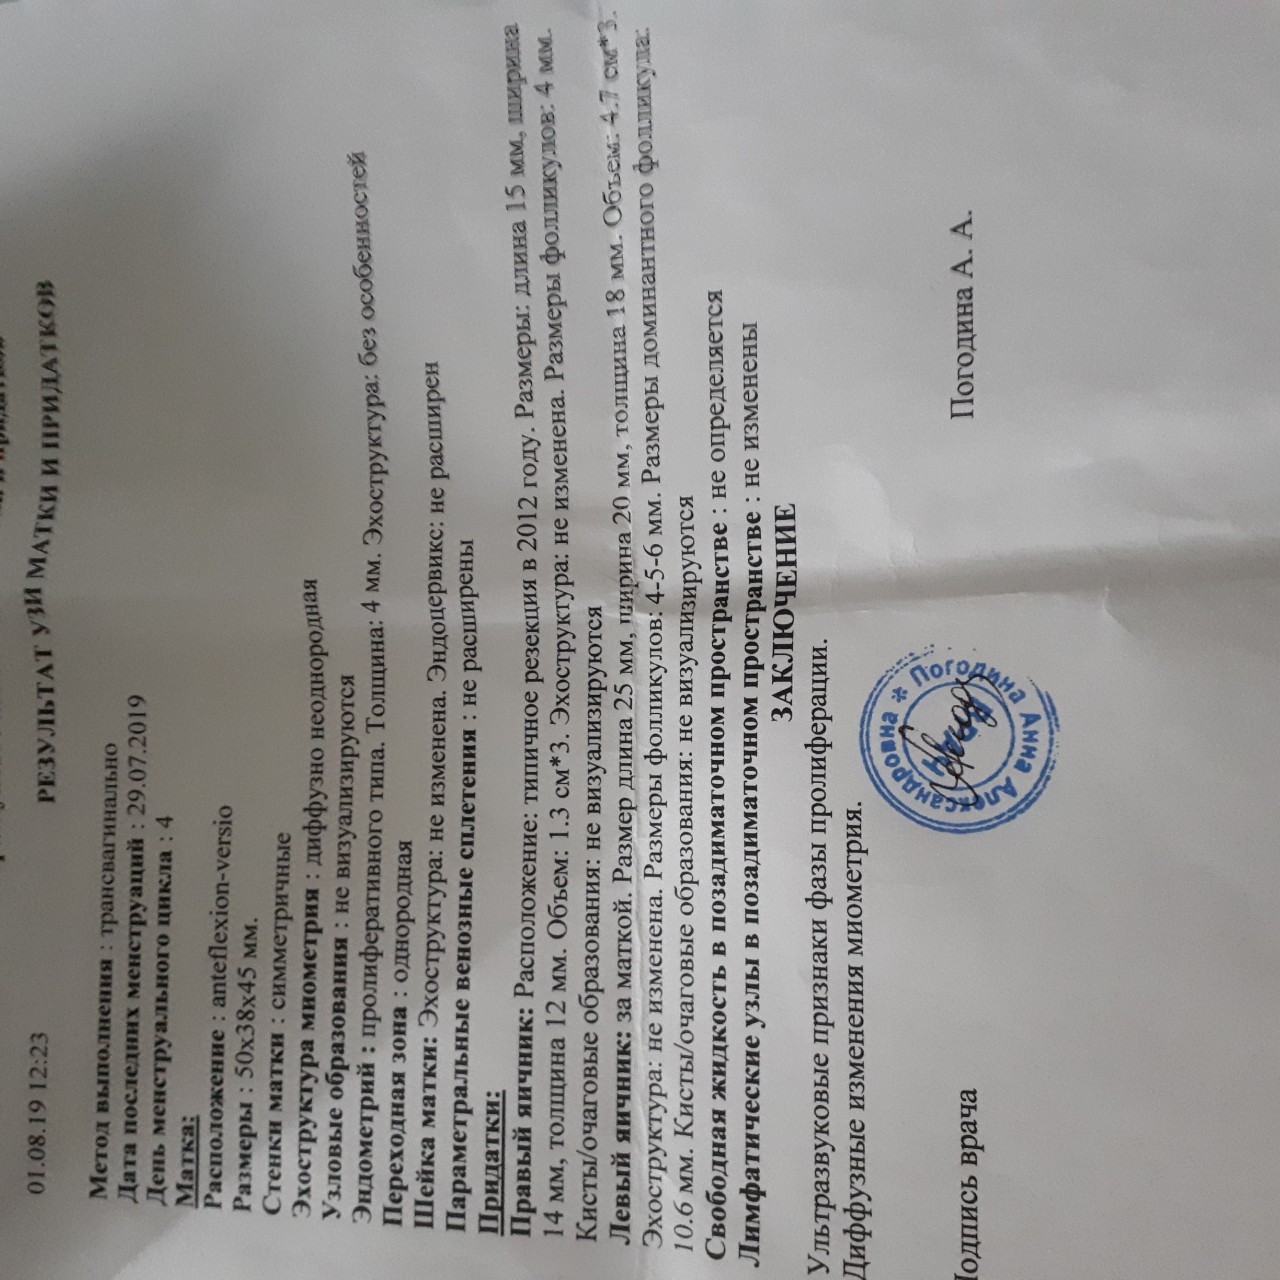

Примеры фото МРТ малого таза у женщин

Ниже представлены примеры фотографий МРТ малого таза у женщин, позволяющие увидеть, как выглядят снимки и какие изменения могут быть обнаружены специалистами.